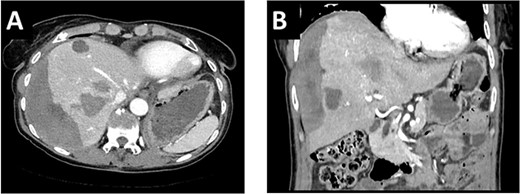

After multidisciplinary tumor board (MDT) discussion, neoadjuvant chemotherapy with six cycles of FOLFOXIRI and Bevacizumab followed by liver-first approach was decided. Restaging after 3 months showed stable disease of the CRLM, therefore, chemotherapy was continued. After 12 cycles, restaging revealed a size reduction of 12% of the CRLM (Fig. 1B). CEA decreased from 69 to 6.1 ug/l. The patient was then admitted to our department for the evaluation of a curative intent CRLM resection. The radiological work-up revealed three remaining metastases on the left- and seven on the right hemiliver. Volumetry illustrated a standardized FLR (sFLR) for a right hemihepatectomy of 30%. In an MDT and the patient was deemed amenable to ALPPS surgery due to the marginal sFLR, bilobar metastases and exceptionally good performance status. Preoperative liver function tests showed normal liver function (LiMAx 450 mcg/kg/h, cut-off >315 mcg/kg/h and ICG R15: 4.0%, cutoff <12%). Although liver biopsy is not routinely performed before ALPPS, MDT recommended a biopsy of the healthy liver to rule out chemotherapy-associated steatohepatitis after 12 cycles of FOLFOXIRI and Bevacizumab in order to ensure a safe liver resection. The biopsy showed signs of subacute hepatocyte demise without fibrosis or cirrhosis. The day after the liver biopsy, the patient collapsed and was admitted to the emergency department of another hospital. CT scan showed a large intrahepatic hematoma (Fig. 2) without active bleeding probably secondary to the biopsy procedure. Due to a hemoglobin drop of 12 g/l a day later and the enlargement of the hematoma in follow-up CT scan, the patient was admitted to angiography, which showed several subcapsular liver bleedings, therefore the right hepatic artery was embolized. Luckily, an accessory right hepatic artery arising from the superior mesenteric artery was present. This enabled us to stay on track with the ALPPS procedure as the right hemiliver would be otherwise without any blood supply (Fig. 3). In synopsis of those findings, the operation was scheduled.

(A/B) CT-scan showing a large intrahepatic hematoma after liver biopsy on the right side.